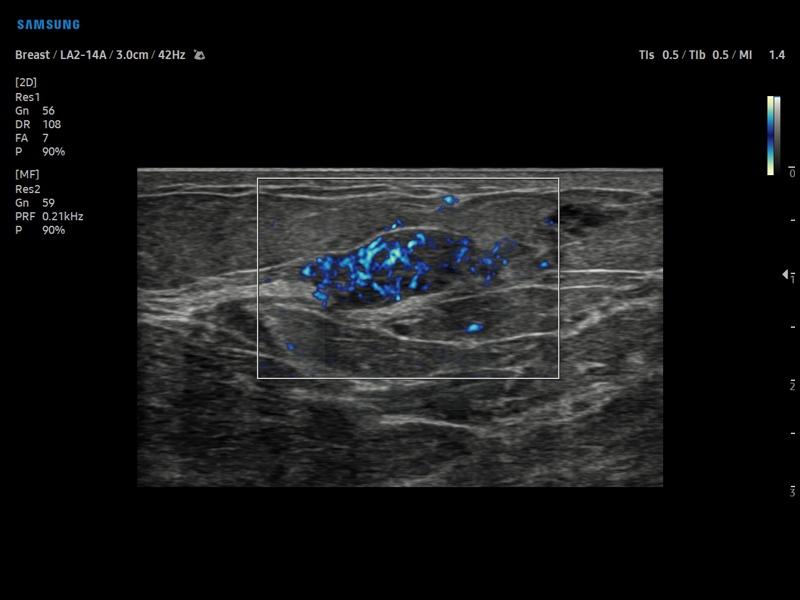

Функция MV-Flow™ визуализирует медленный кровоток в микроциркуляторном русле, маркируя цветом его интенсивность.

Режим MV-Flow - узел в молочной железе